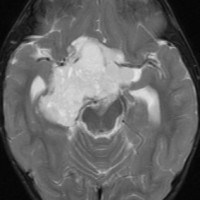

幼児の視路の毛様粘液性星細胞腫です。T2強調画像(左側)で白く高信号に写るのが特徴です。ガドリニウム増強ではまだらになっていますが,均一に真っ白に高信号になることも多いです。乳幼児のものは,ドロドロに柔らかい腫瘍です。

生後7カ月の幼児です。目が揺れるようになり(振り子様眼振)眼科を受診して腫瘍が発見されました。小児脳腫瘍の治療ができる病院へと紹介されました。

1ヶ月後にまたMRI検査がされました。乳児ですから検査にも麻酔が必要です。腫瘍は明らかに大きくなっています。左視神経から視索の腫瘍化が著しいので右側だけかすかに視力が残っているかもしれません。視力は明かりがわかる程度(明暗弁)と評価されました。

こんなことを書くのは悪いことかもしれませんが,まったく馬鹿げた提案です。この画像はどこをどう見ても視路から発生した毛様粘液性星細胞腫です。画像はpathognomonic(日本語で火を見るよりも明らか)です。この小さな子に,全身麻酔をして開頭手術で生検病理診断すれば,それだけで3週間は化学療法の開始が遅れます。その間に明かりも見えなくなってしまう(完全失明する)可能性が高いでしょう。2021年時点でも,開頭手術による生検術は行われていますが,こんな重病の小さな子どもの頭を無用に開くなど,私にはもう理解不能です。

乳幼児時期には,病理組織像が毛様粘液性星細胞腫で,MRI T2で均一な高信号になりガドリニウムで強く増強されます。腫瘍の増大速度は速く,稀には髄液播種することもありそれが腫瘍死の原因となることもあります。奏効率の高い化学療法を早く開始する必要があります。